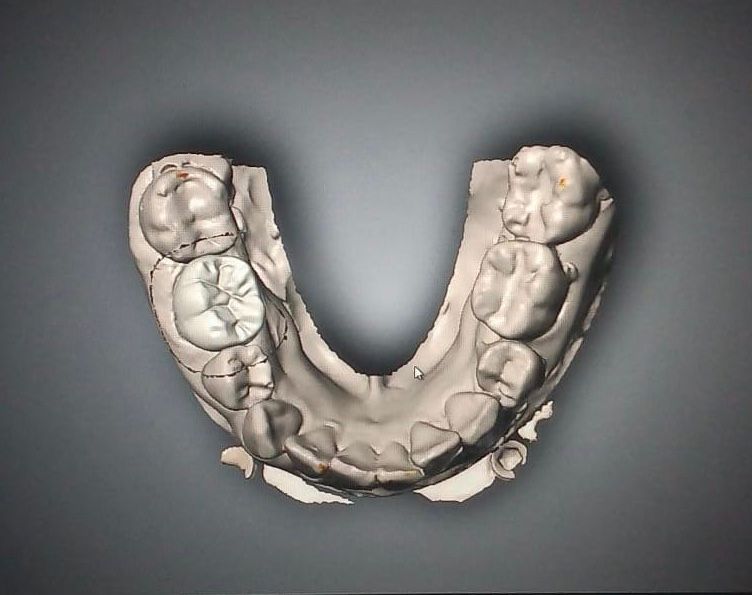

Contamos con tecnología de punta que nos facilitara el diagnostico y tratamiento de tu problema dental lo cual hará mas predecible el éxito a largo plazo.

• Implantología dental

• Prótesis dental